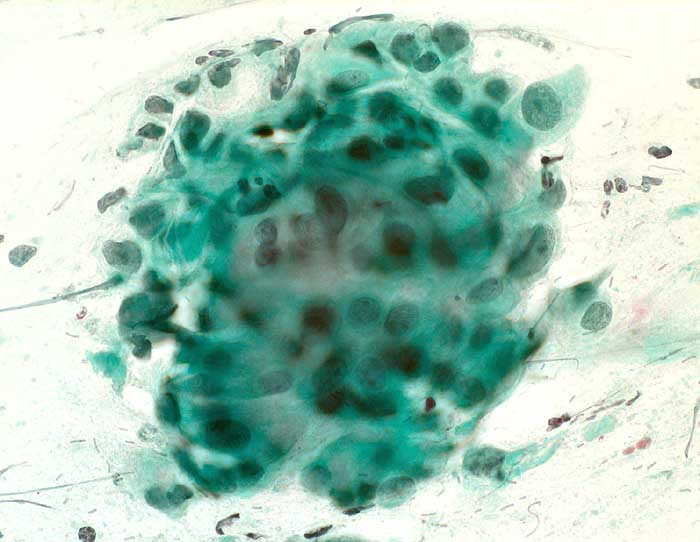

Portioabstrich: mehrere sehr grosse Kerne mit Zylinderzellen und Nacktkernen. Chromatin normal, fein und regelmässig verteilt. Keine vergrösserten Nukleolen.

Zytologische Diagnose: Unverdächtig. Reaktive Zellveränderungen mit vergrösserten Kernen, wie unter Gestagen-Behandlung.